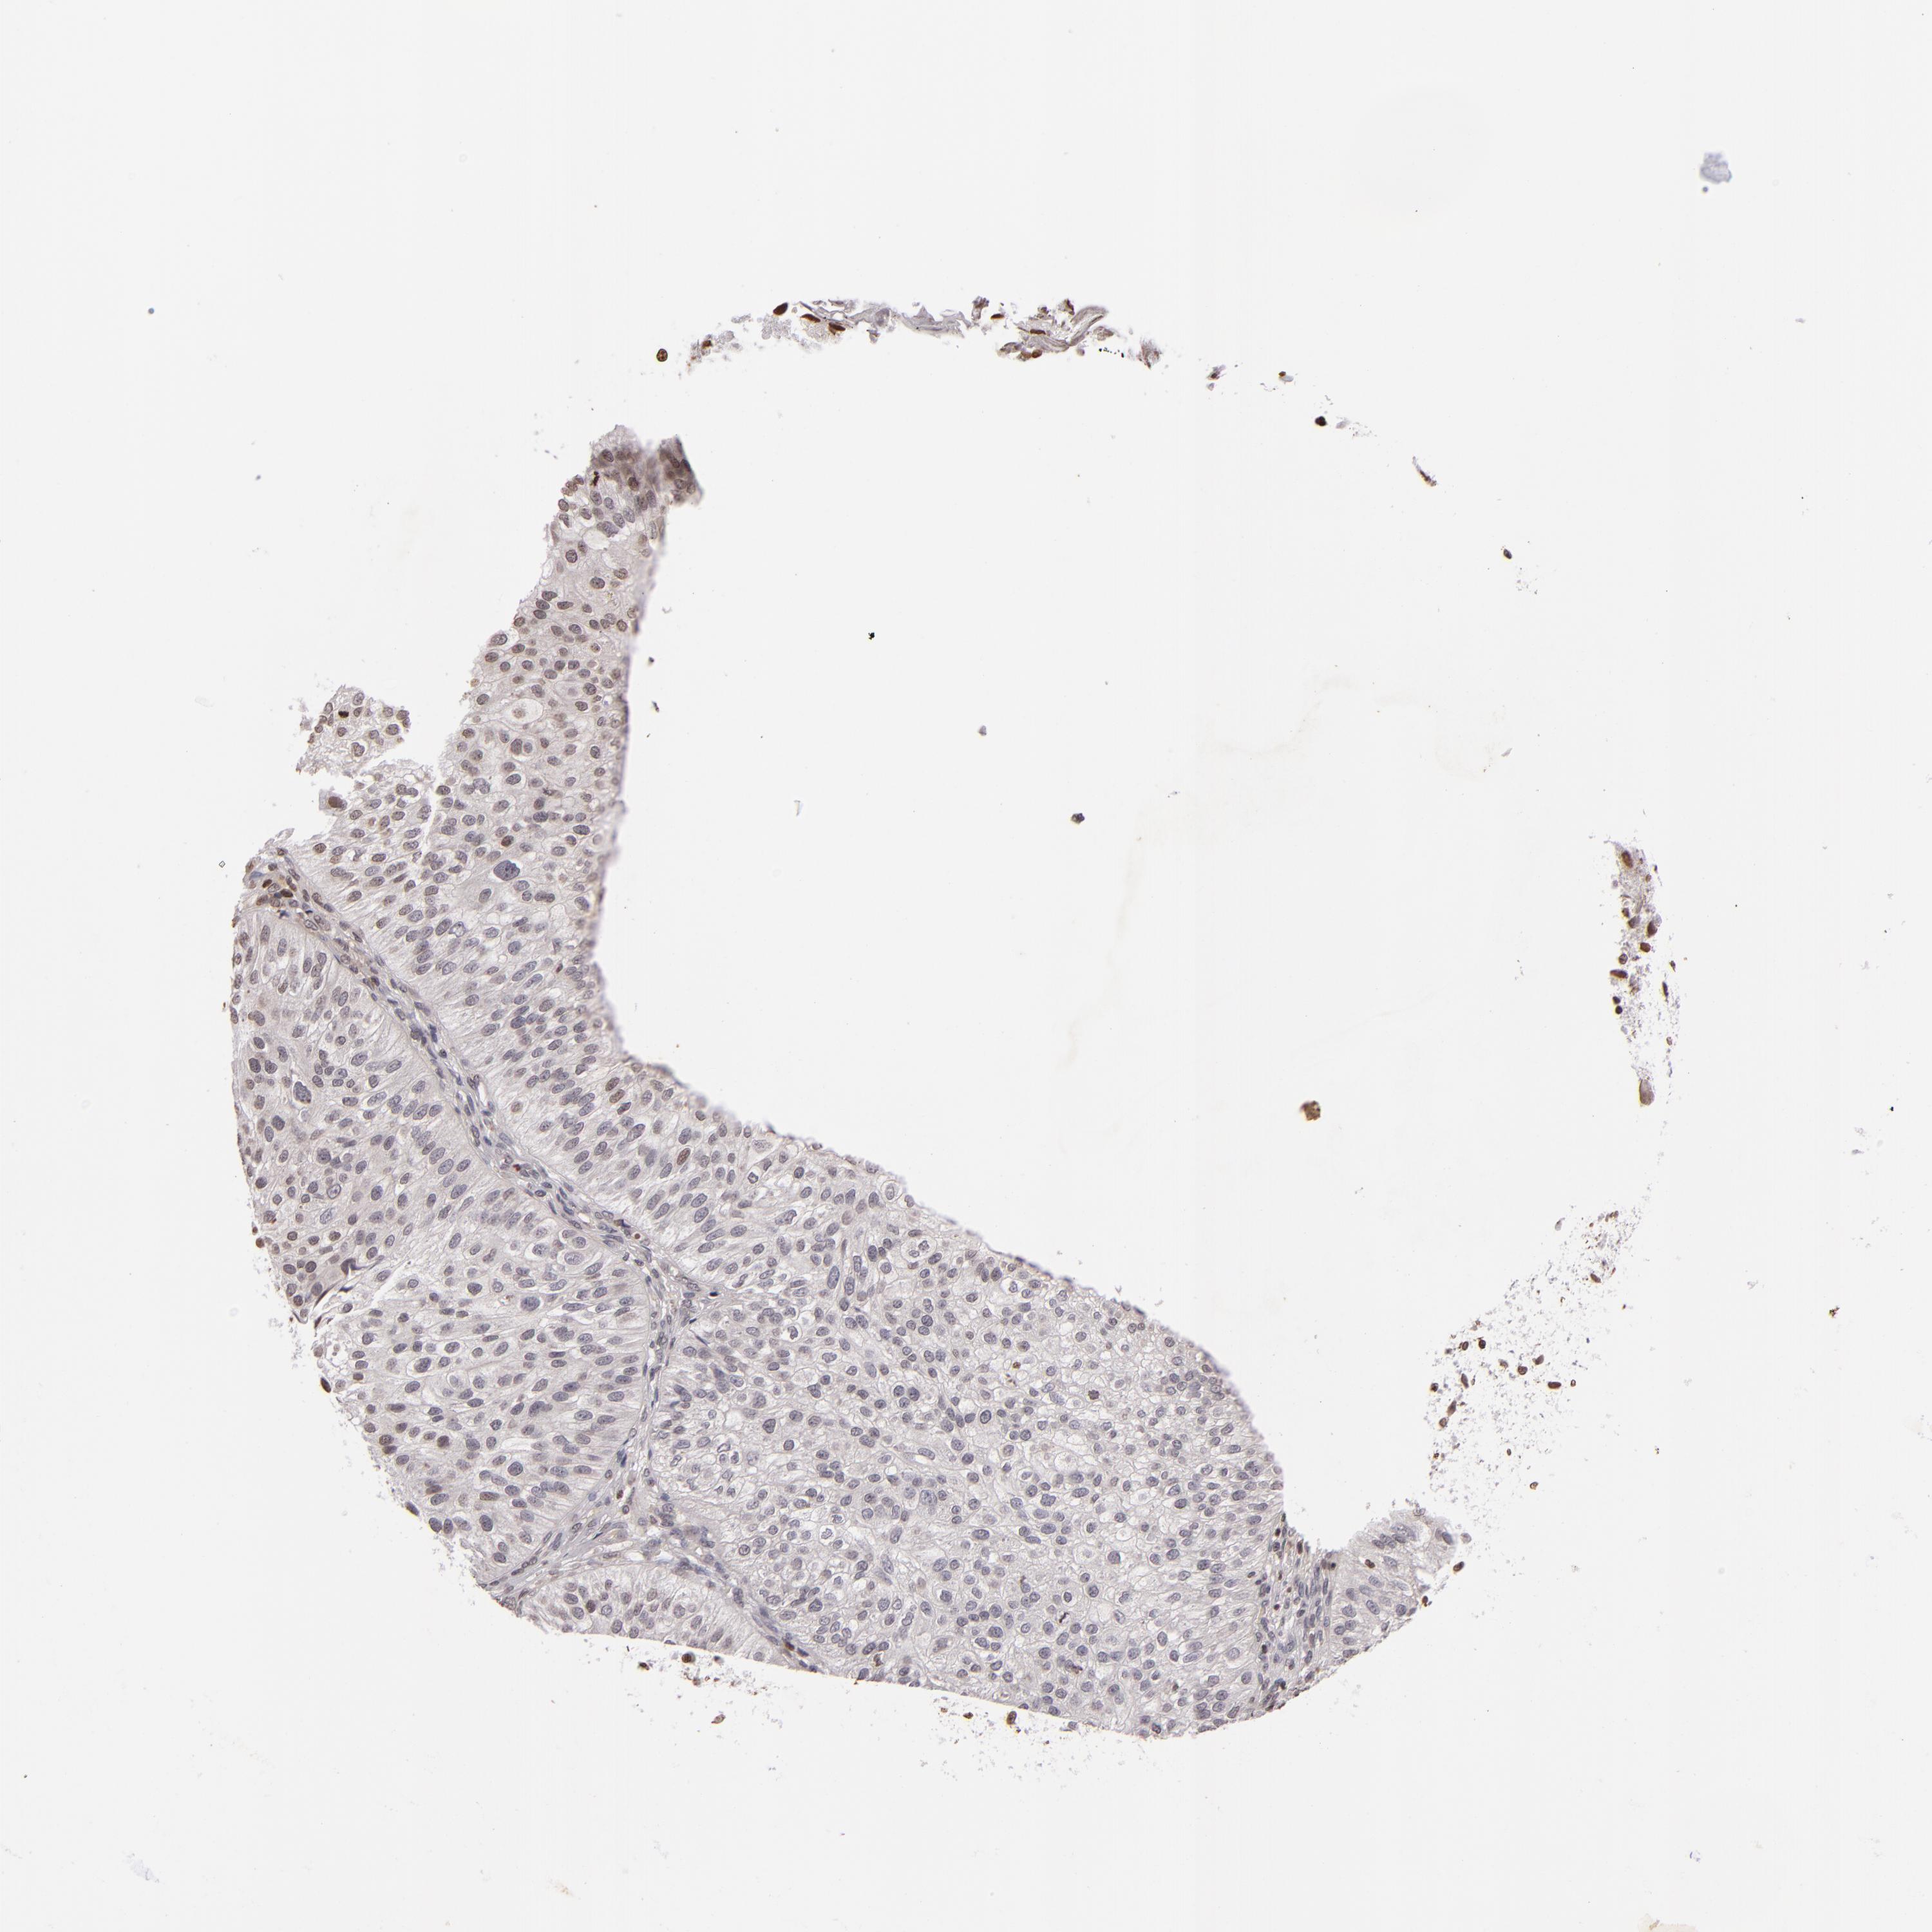

UROTHELIAL CANCER - Protein expressioni

A mouse-over function shows sample information and annotation data. Click on an image to view it in a full screen mode. Samples can be filtered based on level of antibody staining by selecting one or several of the following categories: high, medium, low and not detected. The assay and annotation is described here.

Note that samples used for immunohistochemistry by the Human Protein Atlas do not correspond to samples in the TCGA dataset.

Antibody stainingi

Antibody staining in the annotated cell types in the current human tissue is reported as not detected, low, medium, or high, based on conventional immunohistochemistry profiling in selected tissues. This score is based on the combination of the staining intensity and fraction of stained cells.

Each image is clickable and will lead to virtual microscopy that enables deeper exploration of all samples and also displays staining intensity scores, fraction scores and subcellular localization as well as patient and tissue information for each sample.

Antibody CAB002008

Antibody CAB002009

Staining

High

Medium

Low

Not detected

Intensity

Strong

Moderate

Weak

Negative

Quantity

>75%

75%-25%

<25%

None

Location

Nuclear

Cytoplasmic/membranous

Cytoplasmic/membranous,nuclear

Urothelial carcinoma, High grade

Urothelial carcinoma, Low grade

Adenocarcinoma, NOS